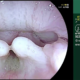

Vellosidades intestinales duodeno

En el video muestra una endoscopia las vellosidades intestinales en duodeno.

El revestimiento epitelial interno del intestino delgado está muy doblado en proyecciones en forma de dedos llamadas vellosidades.

Muchas vellosidades sobresalen hacia la luz intestinal, aumentando en gran medida la superficie disponible para la absorción de los alimentos.